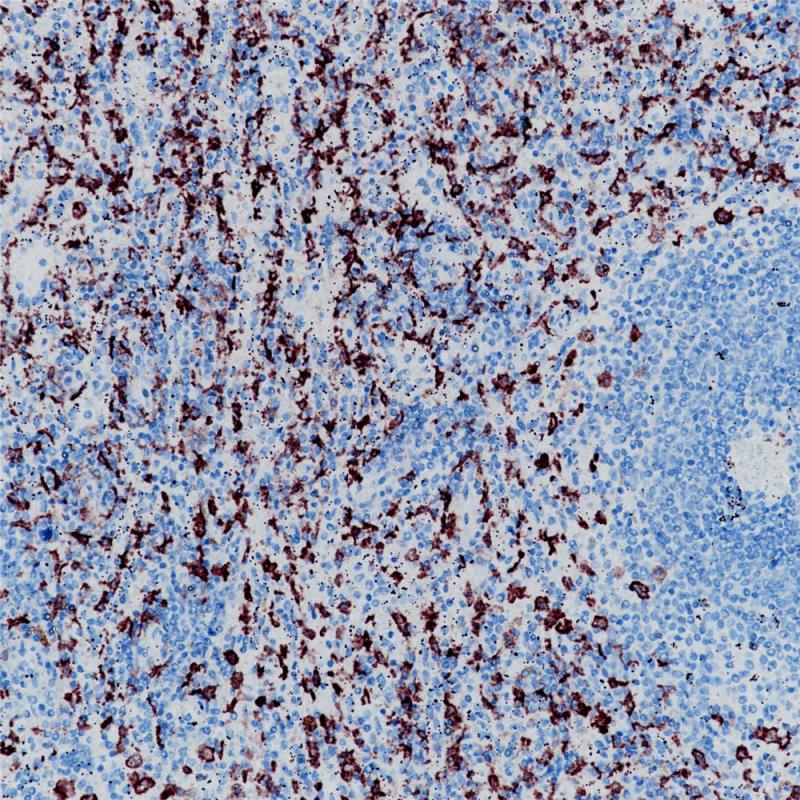

CD163 重组兔单克隆抗体

CD163是I型膜蛋白,属于清道夫受体超家族的成员。CD163是目前最特异的组织细胞标记物,在外周循环的单核细胞以及大部分组织的巨噬细胞中表达,如脾脏树突细胞,肺泡巨噬细胞,肝脏Kupffer细胞。而在一些淋巴滤泡中央的幼稚细胞,套外区域的巨噬细胞、朗格汉斯细胞以及指突状网织细胞中则不表达CD163。肿瘤组织中,CD163在绝大多数AML中的单核样细胞中表达,同时在大部分组织肉瘤、纤维肉瘤、窦岸细胞血管瘤、淋巴结肿大疾病、朗格汉斯细胞增多症、典型和非典型纤维肉瘤以及一些皮肤纤维肉瘤中也有表达。